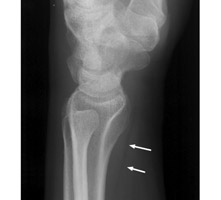

Diagnosis:Wrist Fracture Discussion:A. Normal pronator fat pad. B. Displaced pronator fat pad. Lateral wrist x-ray, a reveals abnormal bulging of a fat plane adjacent to an area of underlying osseous injury. The ventral bulging of the fat plane overlying the pronator quadratus muscle has been coined the "pronator sign." Although it typically means underlying fracture is present, it may also be seen in simple soft-tissue injury of the same region. It is a good sign and should alert the radiologist of possible fracture when present. References: